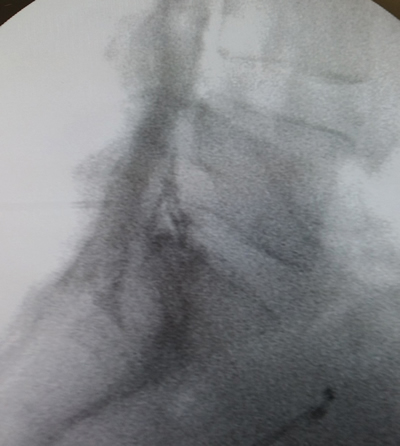

Tablas y Figuras

Figura 2